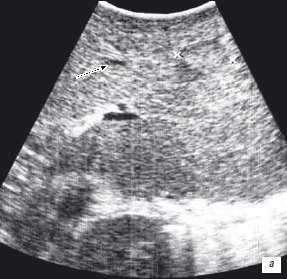

Клинический пример N2. Пациентка Р. находилась на лечении в ГУРОНЦ РАМН. При прохождении обследования был установлен диагноз рак толстой кишки. По данным ультразвуковой компьютерной томографии на фоне выраженной диффузной неоднородности паренхимы печени очаговые образования не определялись. При проведении ангиографии и компьютерной томографии так же убедительных данных за наличие метастазов в печень получено не было. При интраоперационном ультразвуковом исследовании были выявлены два очага, характерными особенностями которых являлись малые размеры (0,2 - 0,4 см), а так же нечеткость контуров и изоэхогенность структуры (рис. 1 а,б).

Рис. 1. Метастатические очаги (стрелки) в печени при интраоперационной ультразвуковой томографии.